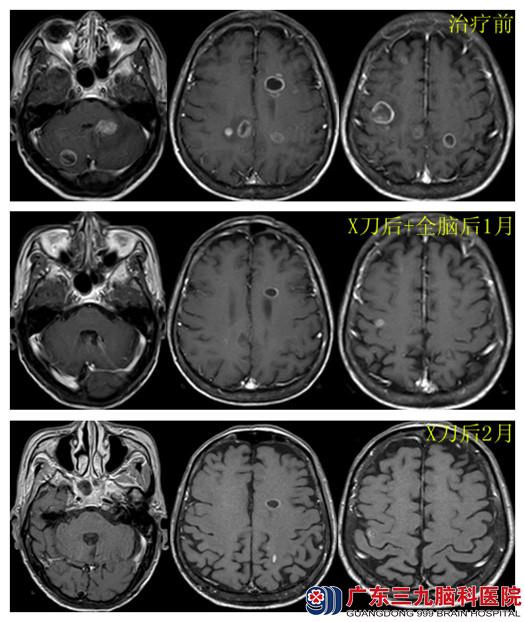

凌先生,66岁,小细胞肺癌3程化疗后半年,左侧肢体无力伴头痛、呕吐10余天,入我院肿瘤综合治疗中心。体征:精神差,卧床,左侧额纹消失,嘴角向左歪斜,伸舌左偏,咽反射迟钝。双肺呼吸音低,左侧肢体感觉异常。左上肢肌力III-IV级,左下肢肌力III级。MR示颅内多发占位。诊断:1.右上肺小细胞肺癌;2.颅内多发转移瘤;3.双下肺肺炎;GCS15分、KPS=40分、ECOG4分。入院后行立体定向无框架SRS治疗功能区4个病灶,中心剂量为800-900cGy,2天后肢体肌力开始好转,后开始WBRT,DT 30Gy/15f,病情进一步好转。

典型病例3:

李女士,56岁,因左侧上肢进行性乏力2周入院。患者三年前因腰背部痛1月在外院行“左侧全肺切除术+纵膈淋巴结清扫术”,术后病理示:小细胞肺癌。术后行6程EP化疗,术后约一年出现左手指无力,进行性加重,逐渐出现左上肢无力,行CT示颅内多发脑转移,转来我院肿瘤综合治疗中心进一步治疗。查体:左上肢肌力III级,肌张力不高。入院后行SRS,确定5个病灶,中心剂量为1350-1400cGy,体积0.5-14mm3,治疗后第3天自诉左上肢肌力好转,后行全脑放疗及6程EP化疗。放疗后2年复查KPS100分。